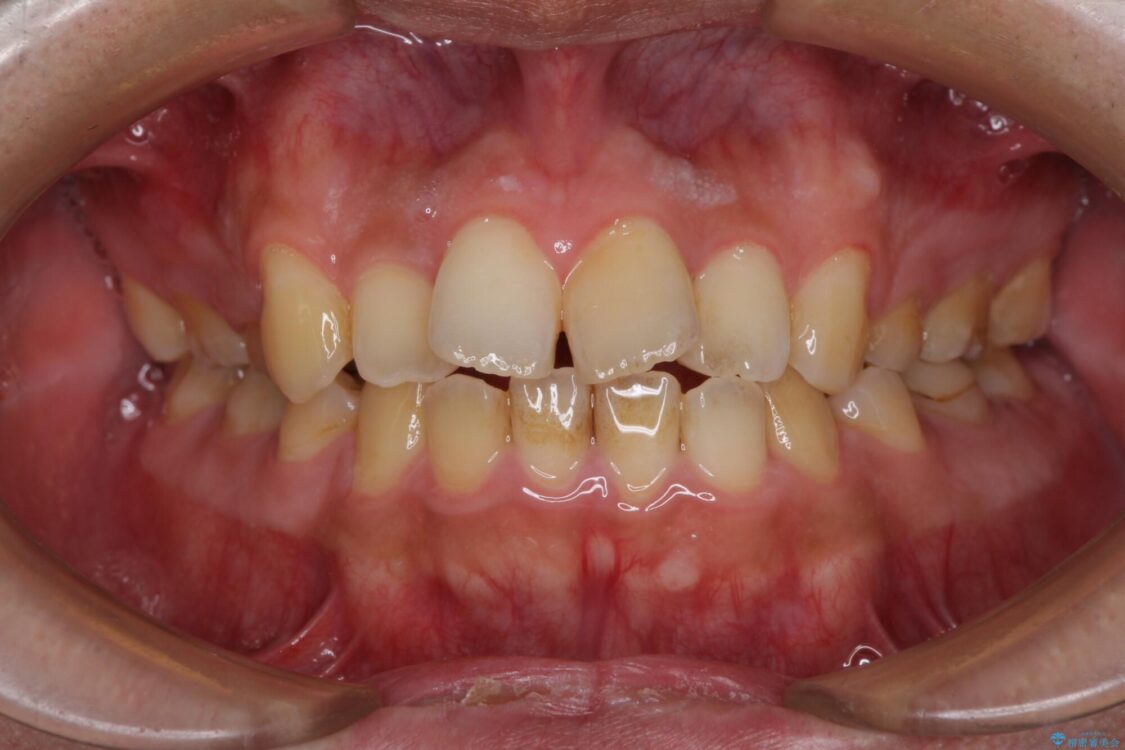

治療後

• 後戻りでデコボコの前歯 インビザライン矯正治療 治療後画像